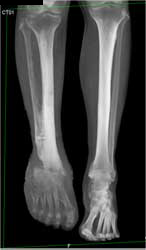

Diagnosis

Pectus Deformity